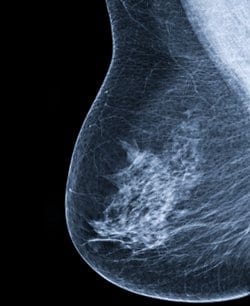

לאורך 19 שנות המעקב, 5% מהנשים אובחנו עם סרטן שד פולשני. לאחר תקנון למשתנים מתערבים מרובים, נמצא כי נשים עם תדירות גבוהה של VMS מציגות סיכון גבוה ב- 13% ללקות בסרטן השד, בהשוואה לנשים שלא חוו VMS.